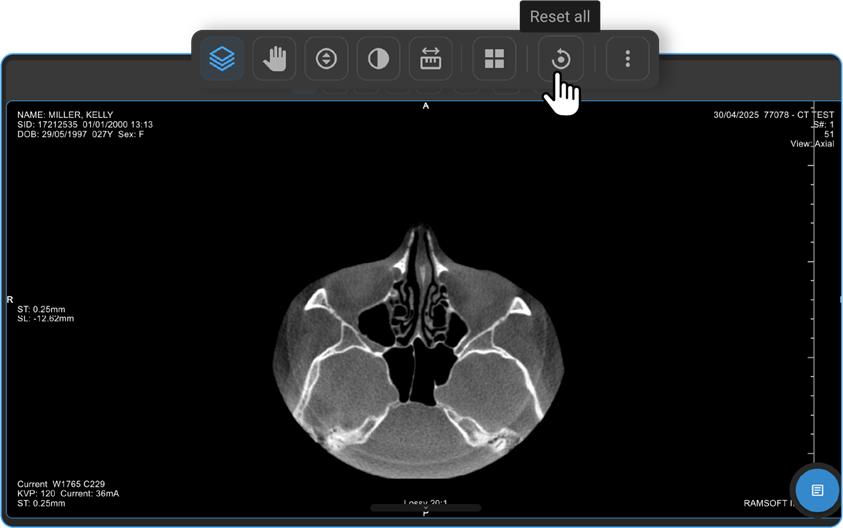

How Do I Reset All Changes?

- The Reset All option appears on the toolbar only if you’ve applied changes.

- Click it to revert everything to default.

- Once reset, the option disappears.